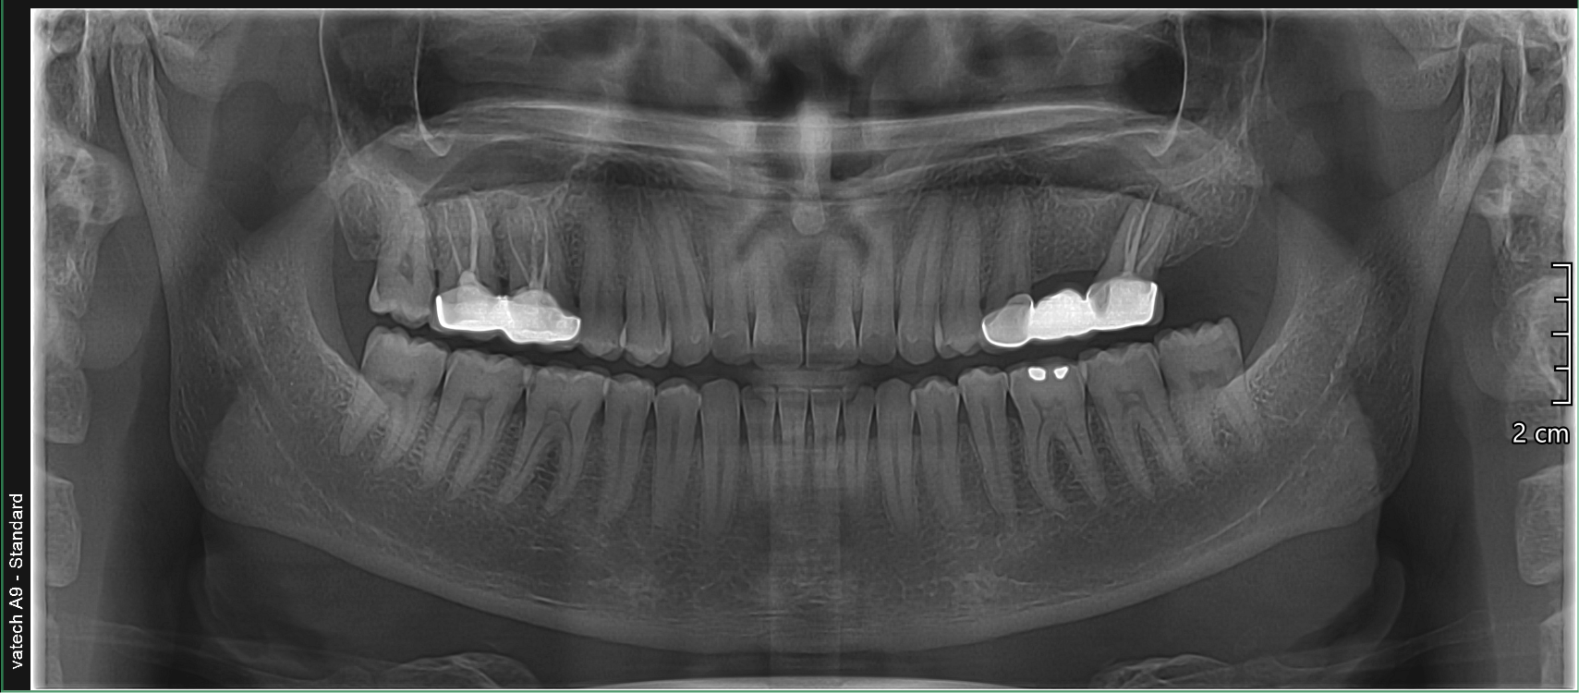

The Vatech A9 provides the most precise & high-quality panoramic images by combining image processing & accumulated experience in dental imaging from vatech. This will increase your diagnostic accuracy for improved treatment planning & patient satisfaction.